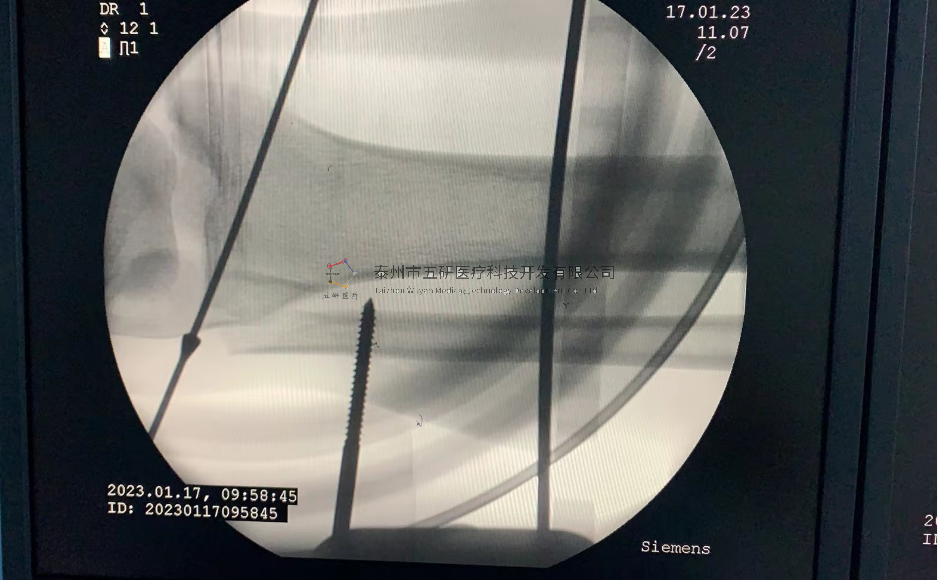

【基本資料】患者,男,65歲

【患者情況】脛骨遠(yuǎn)端骨折伴腓骨骨折

【影像圖片—術(shù)前】

【影像圖片—術(shù)后】